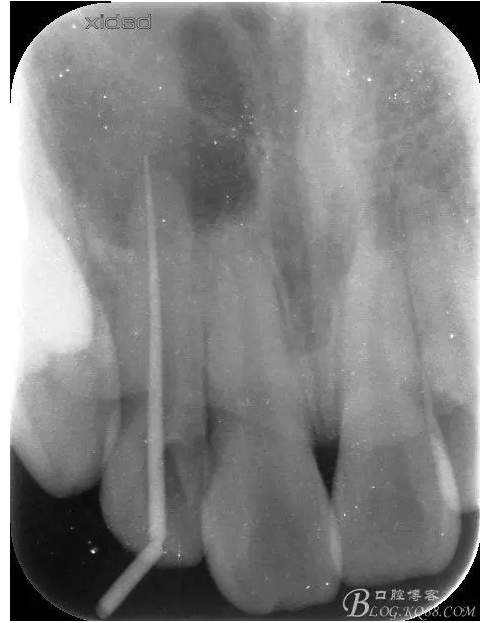

1.術(shù)前的根尖片檢查及根管治療影像:

圖2.根管治療術(shù)后直接局部 麻醉下切開、翻瓣,發(fā)現(xiàn)12唇側(cè)骨壁有綠豆大小骨缺損